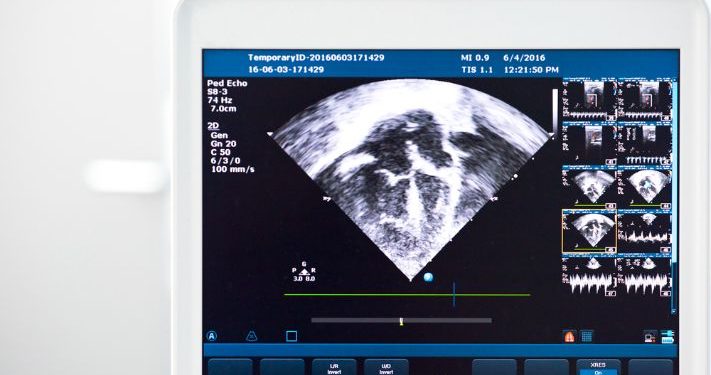

A doctor can diagnose tricuspid stenosis with a physical examination and an echocardiogram. Your doctor will also check your chest x-ray and your electrocardiogram to look for any other problems with the heart.

On an echocardiogram, the doctor will see that your tricuspid valve is leaking or leaking backward into the upper chamber of your heart (right atrium). Your doctor may also be able to hear a murmur during the heart’s normal rhythm that sounds like blood is coming back into your tricuspid valve.